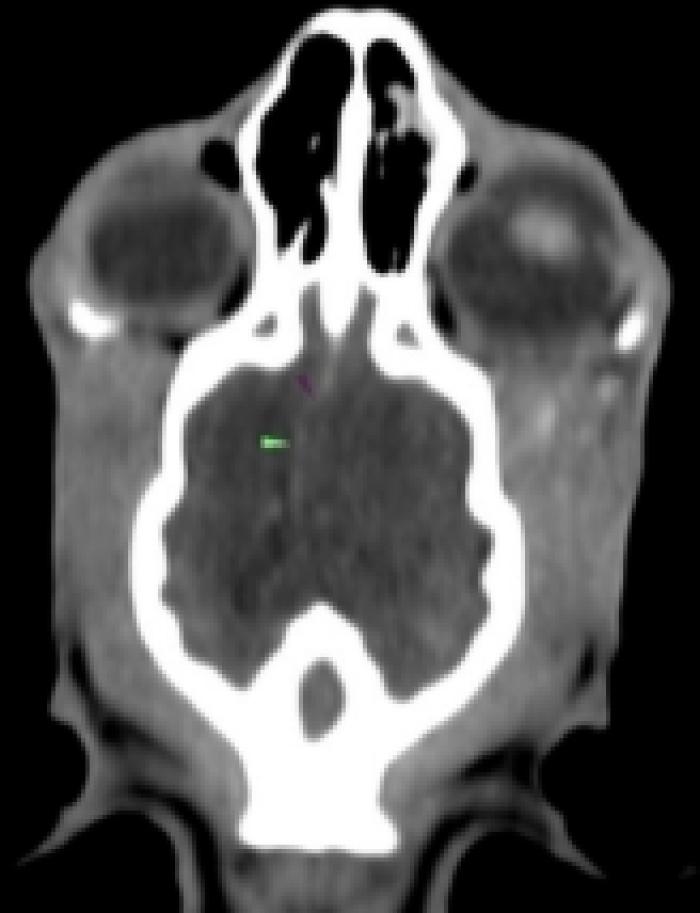

Revisión clínica y control analítico (día 35): a pesar del tratamiento instaurado, el paciente acude de urgencia debido a que el cuadro progresa con signos neurológicos centrales: marcha en círculos, pressing, anisocoria (pupila izquierda miótica y derecha midriática), respuesta a la amenaza y reflejos pupilares directos e indirectos negativos bilateralmente. El paciente no presenta hipertensión ni alteraciones en el fondo de ojo. Se repite hemograma, con empeoramiento del leucograma y fructosamina, con valor nuevamente más bajo, modificándose la pauta de insulina a 2 UI/12 h (Tabla 2) y se añaden ecografía abdominal (sin alteraciones relevantes) y bioquímica completa con parámetros hepáticos (transaminasas, bilirrubina y ácidos biliares pre-prandiales), lipasa específica felina y tiroxina total en rango fisiológico. Ante la sospecha de infección intracraneal, se añade a la pauta de antibioterapia trimetoprima-sulfametoxazol a dosis de 15 mg/kg/12 h y se realiza tomografía computarizada (TC) de cráneo.

TC: efecto masa compatible con absceso, ocupando senos frontales, con osteomielitis del hueso frontal derecho, miositis y absceso en musculatura temporal derecha en contacto con hueso frontal, afectación intracraneal en área epidural del lóbulo temporal derecho con desviación de línea media de hemisferios (sin afectación de parénquima). Se observa además moderada pérdida de cornetes nasales en cavidad nasal derecha, sin secreciones asociadas y linfadenopatía regional derecha de tipo reactivo (Figura 6A-F). Se drena el contenido del absceso más superficial y se envía al laboratorio externo para su estudio microbiológico (cultivo y antibiograma).

Absceso epidural en lóbulo temporal derecho, con posible origen en senos frontales, miositis y osteomielitis.